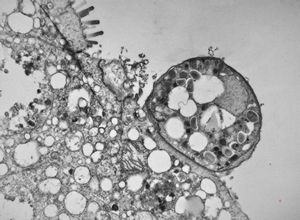

M,33y. | microsporidiosis (or cryptosporidiosis) - duodenum-posttransplantation immunodeficiency